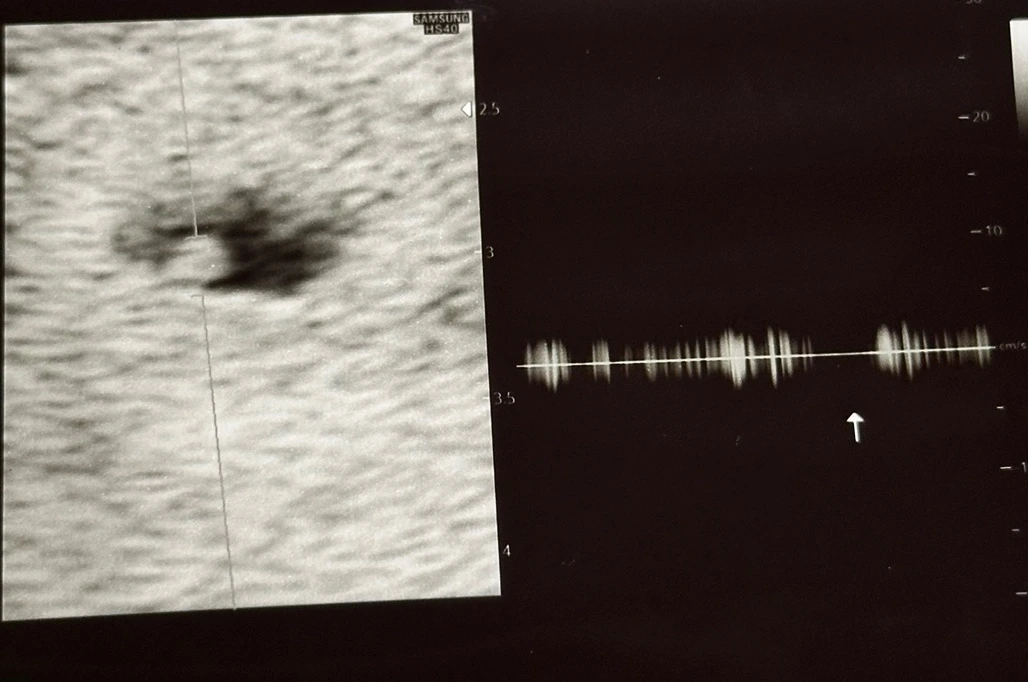

생긴 지 얼마 되지 않아 심장소리는 듣지 못했고 규칙적으로 뛰는지만 확인했다.